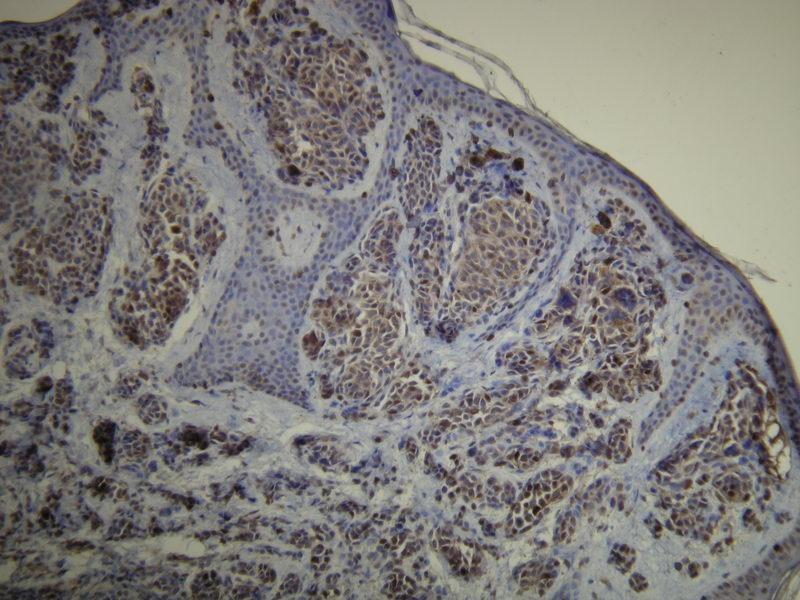

The 兔 单克隆 anti-S-100 antibody is suitable to detect S-100 in samples from 人. It has been validated for IHC (p).

Immunohistochemistry (Paraffin-embedded Sections) (IHC (p))

Peptide derived from N-terminal sequence of human S100-A1 protein. Antibody recognizes the epitope between Val55 - Glu74.

S-100 is a low molecular weight protein expressed in glial cells, chondrocytes, macrophages, Langerhans cells, dendritic cells, adipocytes, keratinocytes and breast epithelial cells. S-100 is involved in regulation of protein phosphorylation, calcium homeostasis, cell differentiation, and inflammatory response. In clinical diagnostics, S-100 protein expression is used as a marker of peripheral nerve tumors, astrocytomas, melanomas and clear cell sarcomas.